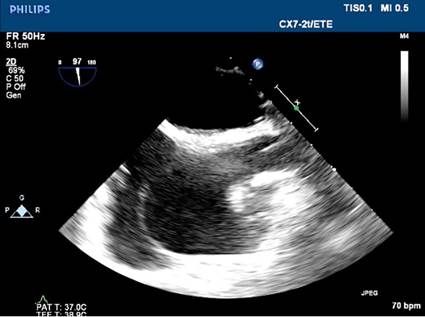

Doppler transthoracic echocardiography (TTE) was performed (Figure 1) which showed dilatation of the right chambers; this,

together with the recent history of trauma surgery, led to the suspicion of

Fig.

1. Transthoracic echocardiogram on

admission. A. Endsystolic apical four-chamber

view. Marked dilatation of right chambers. B.

Parasternal short axis. Right ventricular enlargement with

flattening of the interventricular septum.